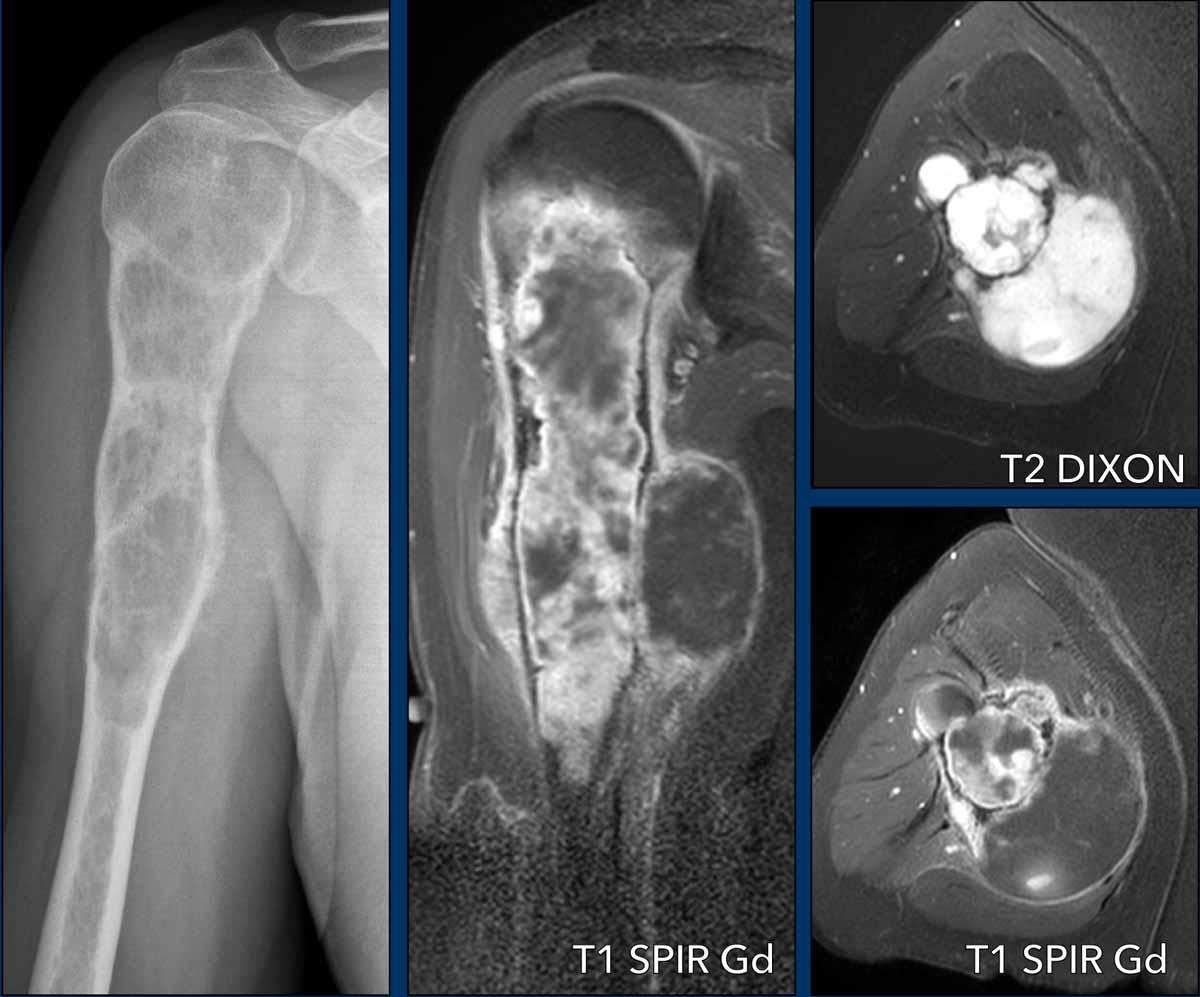

Hình ảnh

Trên phim X-quang, có tổn thương tiêu xương thấm nhiễm với phản ứng màng xương xâm lấn, xói mòn vỏ xương và giãn rộng.

Ảnh T2 DIXON trục ngang cho thấy nhiều khối mô mềm dọc theo xương cánh tay.

Chuỗi xung sau tiêm thuốc cản từ thể hiện ngấm thuốc dạng vách-nốt, viêm màng xương xâm lấn và các vùng nhầy trong khối u không ngấm thuốc cả ở phần gần tủy xương lẫn trong khối mô mềm phía trong.

Kết luận

High grade CS.

MRI xác nhận hình ảnh đa nốt tăng tín hiệu T2 của khối u sụn.

Có một khối mô mềm lớn ở phía trước trong. Có phản ứng màng xương rõ rệt trên MRI, phù tủy xương ở phần gần và phù nề mô mềm xung quanh.

Lưu ý hình thái ngấm thuốc dạng vách-nốt.

Không có ngấm thuốc ở phần trên của khối u và trong khối mô mềm. Đây được coi là thành phần nhầy.

Dựa trên các kết quả MRI, chúng ta nên đưa ra chẩn đoán u sụn ác tính độ II hoặc cao hơn.

Điều trị là cắt bỏ rộng rãi.

Pathology diagnosis: Chondrosarcoma grade III

Thành phần nhầy là một đặc điểm của sarcoma sụn độ cao, có thể nhận thấy bởi cả bác sĩ chẩn đoán hình ảnh lẫn bác sĩ giải phẫu bệnh.

Bác sĩ giải phẫu bệnh cũng đánh giá mật độ tế bào, mức độ không điển hình nhân và số lượng nhân phân chia trong khối u, những yếu tố này cao hơn so với u sụn không điển hình (ACT) hoặc sarcoma sụn độ I.